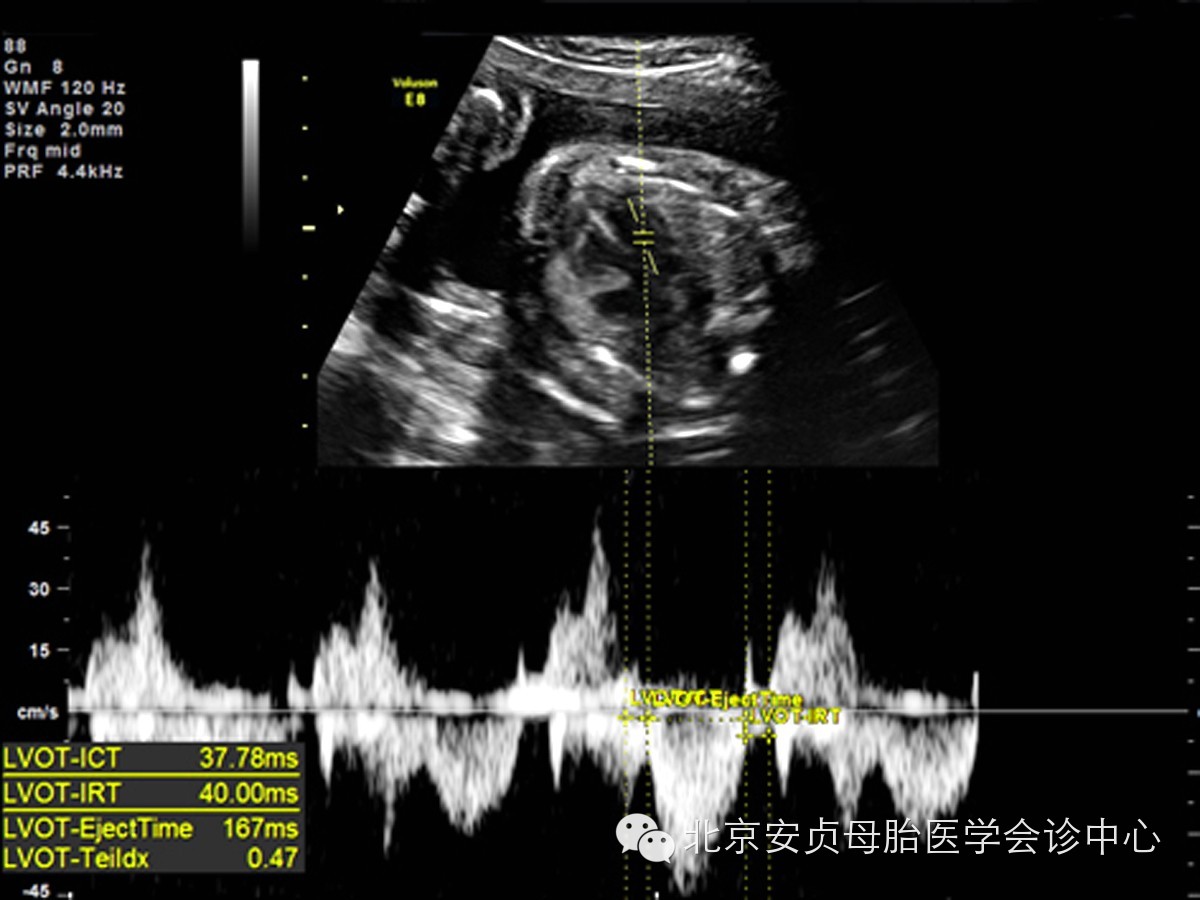

Tei指数不受心腔几何形态改变和心率的影响,是一项检测心功能异常的敏感指标。胎儿心脏收缩和舒张功能处于一个动态发展、相互关联的过程,心功能异常时二者相互影响,因此综合评价二者比较合理。Tei指数= ( ICT + IRT) /ET (注:ICT:心室等容收缩时间,IRT:心室等容舒张时间,ET:心室射血时间)。以频谱多普勒取二尖瓣、三尖瓣、主动脉、肺动脉的血流频谱代入公式进行计算。Tei指数在整个孕周中保持相对稳定范围内,各孕期间无明显差别,正常Tei指数<0.50,Tei指数>0.60为异常。